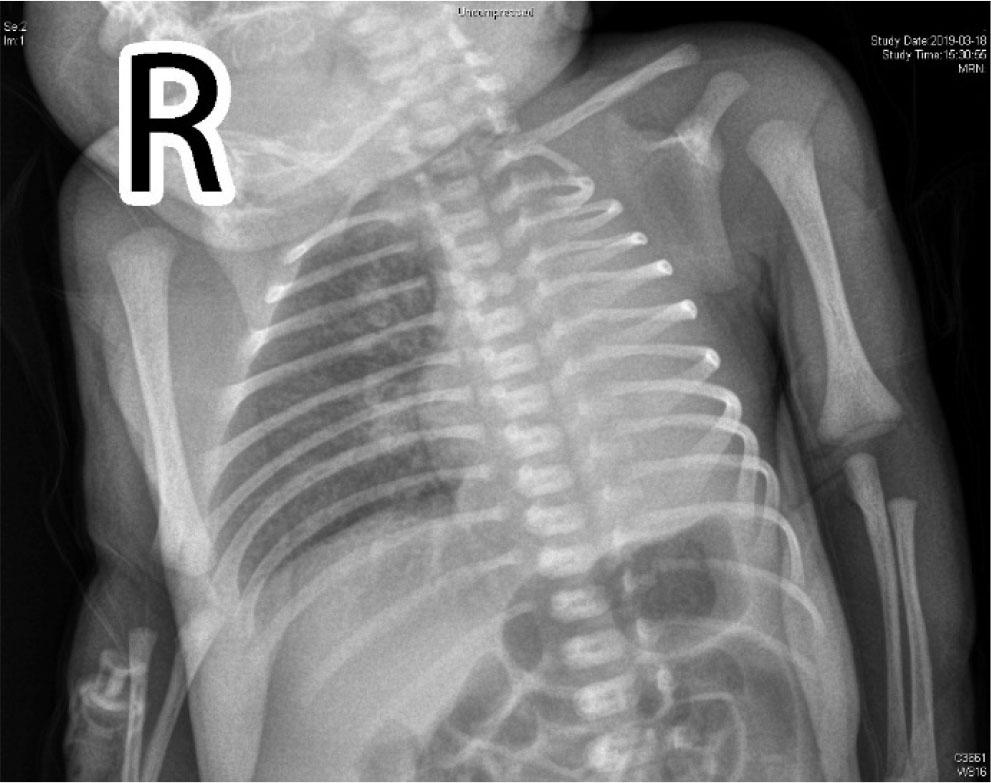

As she showed accelerated breathing, a conventional physical examination was given. There was no respiratory sound in the left lung according to auscultation. Chest film indicated decline in lucency of left lung (Figure 1). Thoracic CT scan was recommended as the size of reduced pulmonary lucency in chest film was too large (Figure 2). On day 3, thoracic CT and pulmonary window indicated absence of left lung and primary bronchus in the left lung. For mediastinal window, there was mediastinal shift to the left side. Structural boundary within left mediastinum was not completely displayed. Three-dimensional imaging indicated extension of trachea, right principal bronchus and bronchus into right lung lobe, while the left lung and left principal bronchus were not visualized (Figure 3). Cardiac ultrasonography confirmed congenital heart disease presenting ventricular septal defect (VSD, 0.18 cm), patent ductus arteriosus (PDA, 0.3 cm × 0.2 cm), patent foramen ovale (0.28 cm), pulmonary hypertension (43 mmHg), mild to moderate tricuspid regurgitation, as well as slight pericardial effusion. Moreover, she showed ectopic kidney. Finally, she was diagnosed with CPH combined with congenital cardiac disease and ectopic kidney.

Bedside chest film indicated lucency decline in the left lung. The pulmonary markings in the right lung were vague.